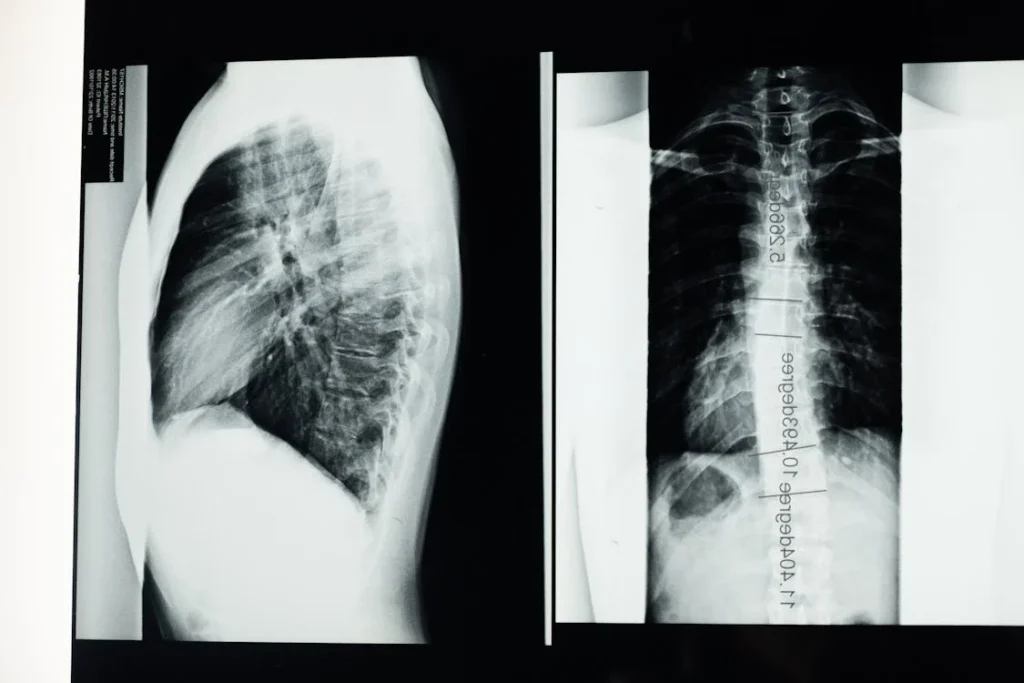

A súlyosabb gerincferdülés esetében a gerinc görbülete olyan mértékű lehet, hogy az a mellkas formáját is befolyásolja. Ez a deformitás a tüdő kapacitásának csökkenéséhez vezethet, ami légzési nehézségeket okozhat. Az érintettek gyakran tapasztalják, hogy nehezebben kapnak levegőt, különösen fizikai megterhelés során.

Ez a probléma nemcsak a tüdőre, hanem a szívre is hatással lehet, hiszen a mellkas deformitása miatt a szívnek is keményebben kell dolgoznia. Ez hosszú távon szívproblémákhoz vezethet, különösen akkor, ha a gerincferdülést nem kezelik megfelelően.